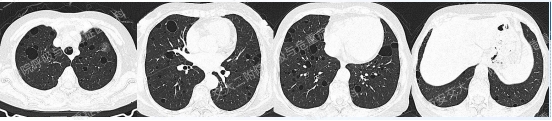

以下2例不同患者的胸部影像改变,又分别考虑什么疾病呢?